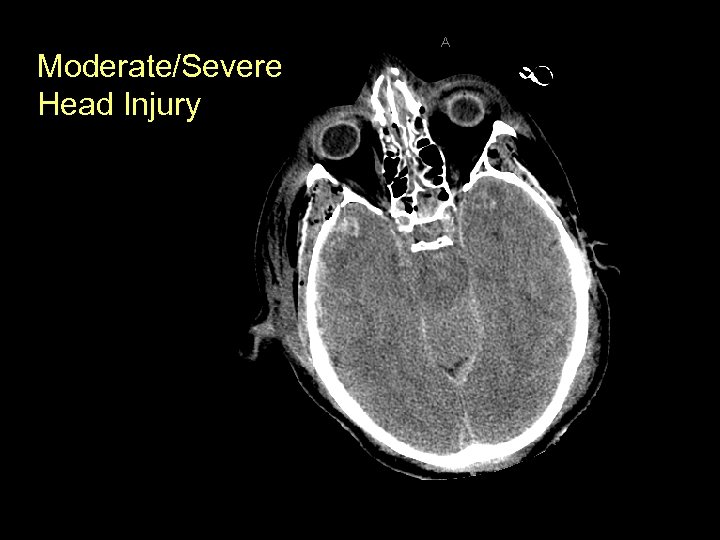

Moderate/Severe Head Injury

Initial Evaluation of Moderate/Severe Head Injury • A, B, C, D, E – Airway control for GCS < 8 – Prevent hypotension and Hypoxia • Hypotension: triples risk of death • Hypoxia: doubles risk of death • Movement in all extremities prior to paralysis if possible • If comatose, assess brainstem function: – Corneal reflex: lightly touch cornea will result in blinking (Cranial Nerves V and VII)

Initial Evaluation of Moderate/Severe Head Injury • GCS ≤ 13 • Immediate CT scan (if stable) • If no CT available, then consult with neurosurgeon and transfer to site with CT • Include cervical spine imaging: CT of the cervical spine recommended the lower the GCS score is